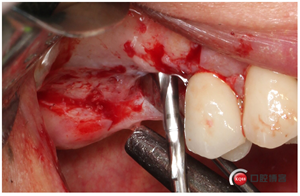

這個東西叫窗口修整鉆,頭兒是圓的且很光滑,四周是有切割功能的,用圓頭頂開上頜竇膜800-1200轉(zhuǎn)速修整窗口邊緣。

我有好的工具我任性,看看我在遠(yuǎn)中用幾秒鐘的時間再開一個窗口。

用大直徑的修整鉆修理邊緣,形成一個規(guī)則的橢圓形窗口。

當(dāng)然了,雖然開始有水壓剝離,但不見得我們需要的位置都能撥開,還需進(jìn)一步剝離一下。然后牙槽嵴頂備洞。

植入骨粉,這時候我們剛才取下的自體骨就派上用場了,加上小牛骨。

同期植入植體。